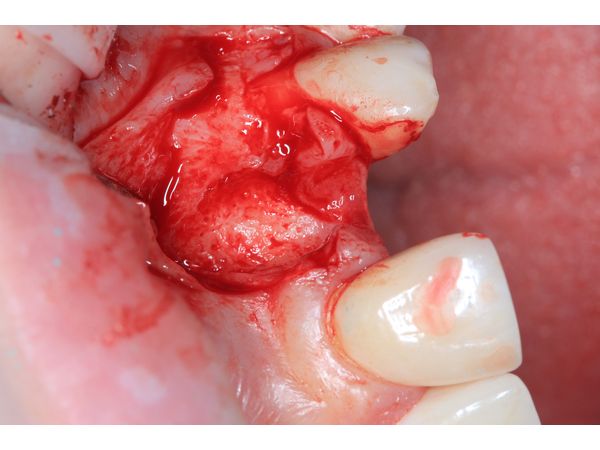

Пациентке сделали анестезию и сформировали микрохирургический доступ для удаления зуба и установки дентального импланта в оптимальную ортопедическую позицию. В зоне дефекта одна треть импланта осталась обнажённой.

Отсутствующую кортикальную пластинку реконструировали с помощью тройного трансплантата из зоны бугра верхней челюсти (забор произвели на стороне вмешательства). Чтобы зафиксировать трансплантат, его утрамбовали в зону дефекта.

Одновременно с этим изготовили временную коронку из пластмассы на титановом основании.